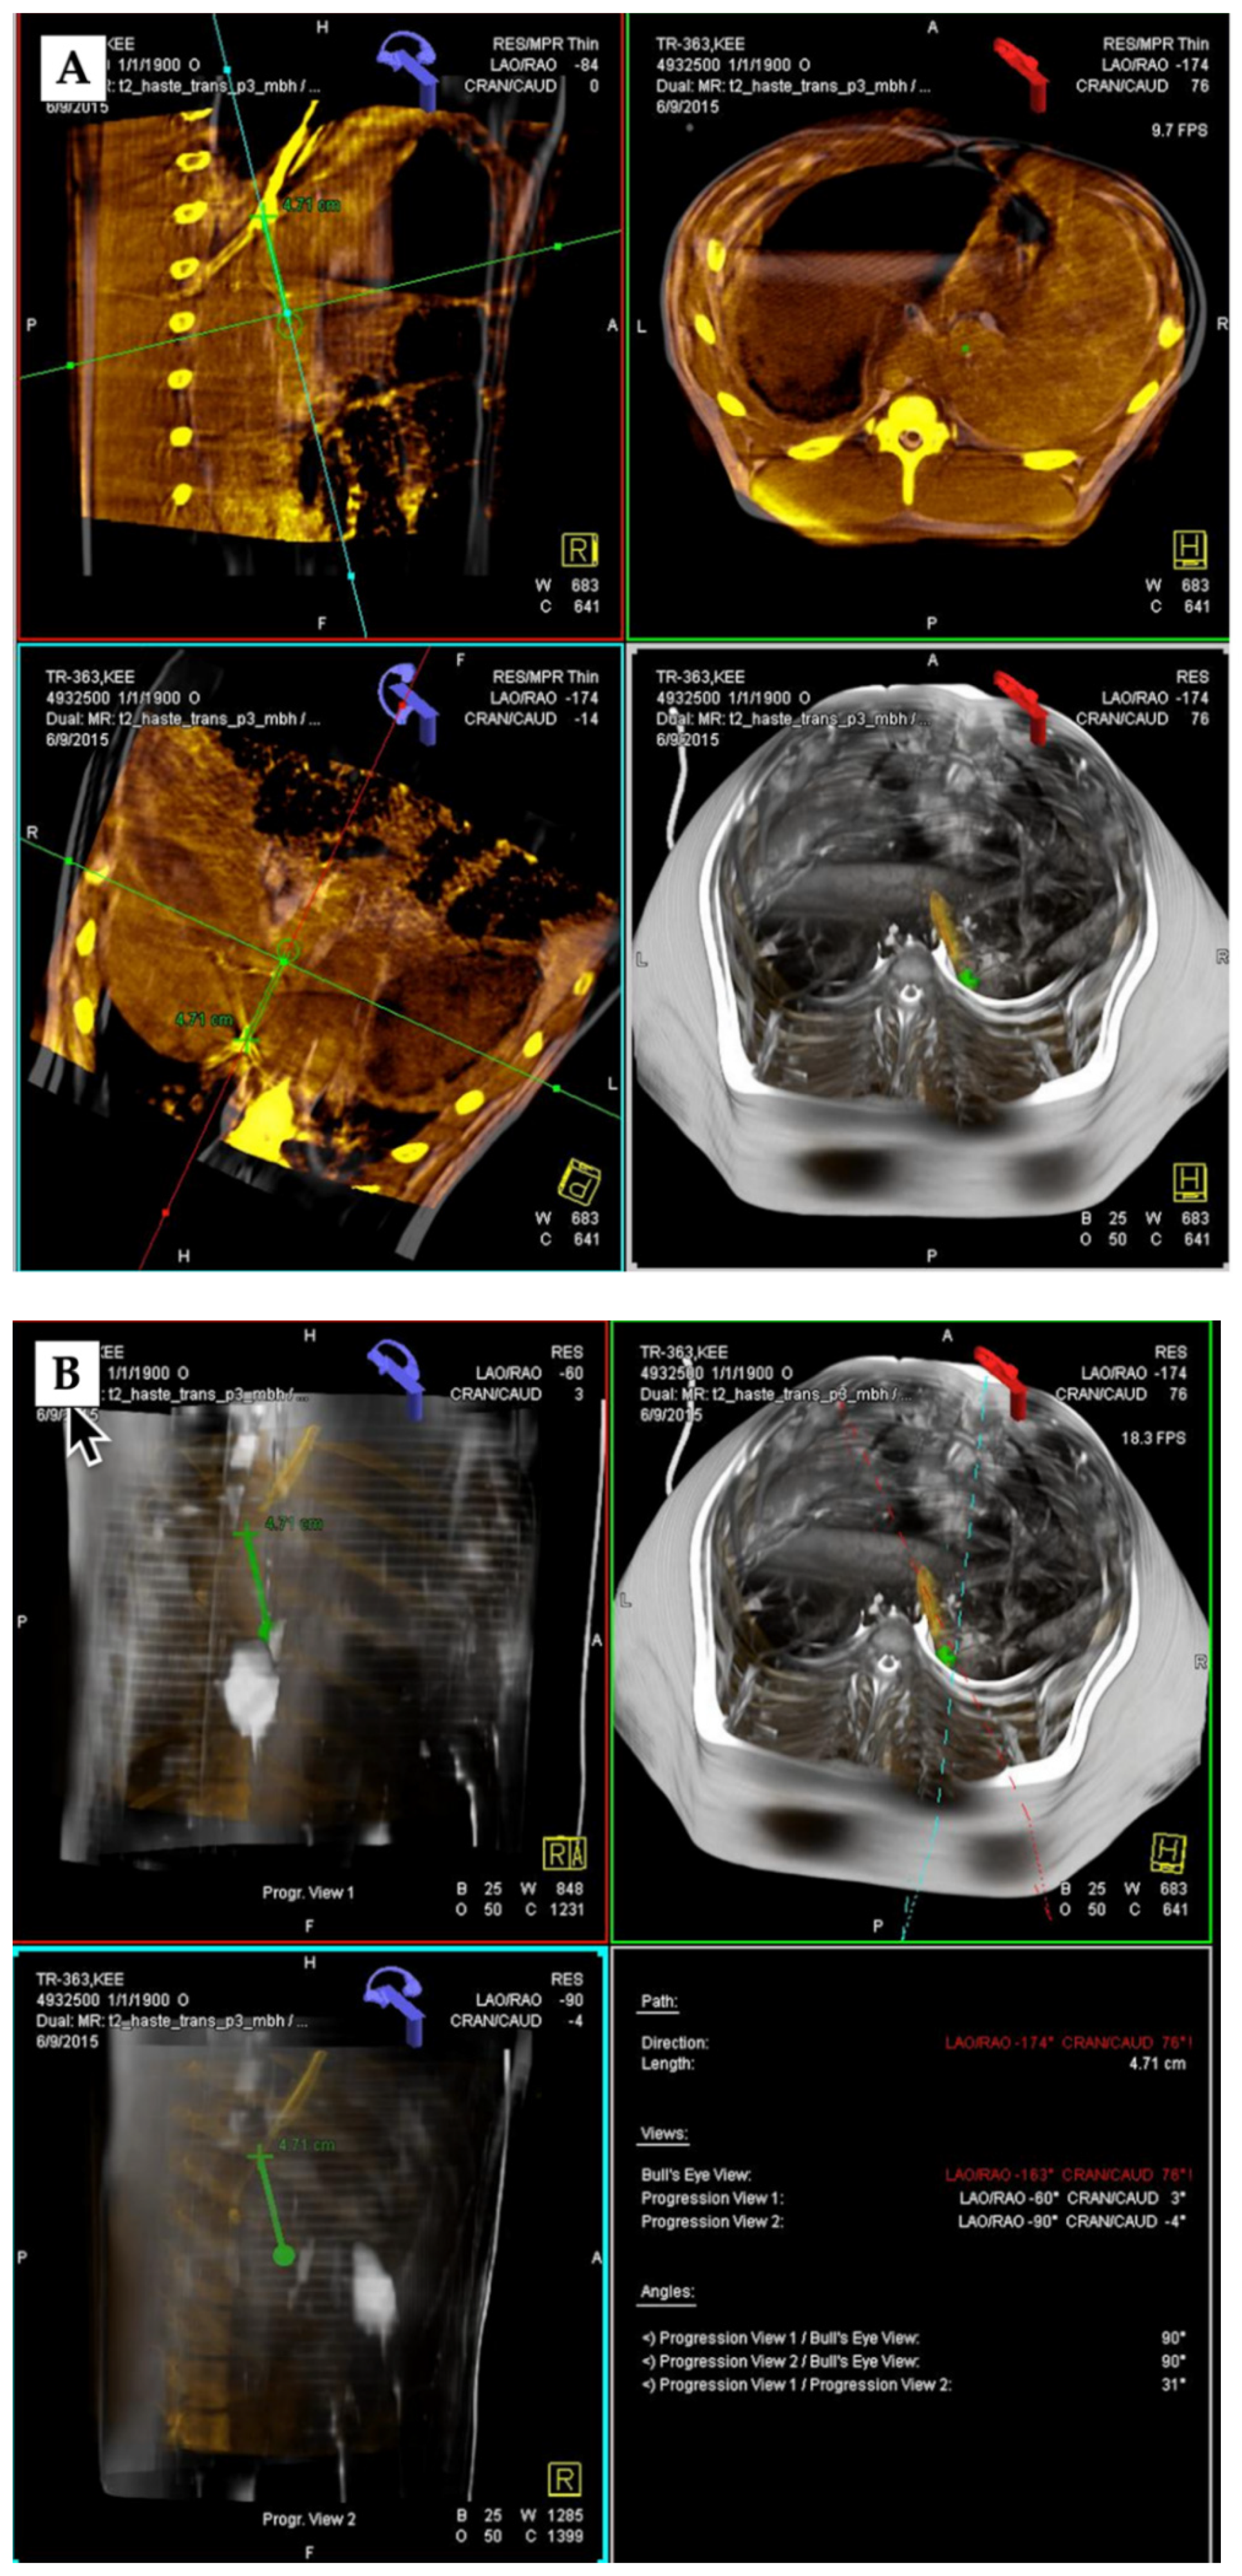

2.5. TIPS and DIPS Creation Using 3D Image Guidance

3.2. 3D Angiography-Guided TIPS Procedure Using Pre-Procedural Cross-Sectional Imaging with CBCT/Angiography-Fused Images

3.3. 3D Angiography-Guided TIPS Using CBCT/Angiography-Fused Images

3.4. 3D Angiography-Guided DIPS Using CT/CBCT/Angiography-Fused Images